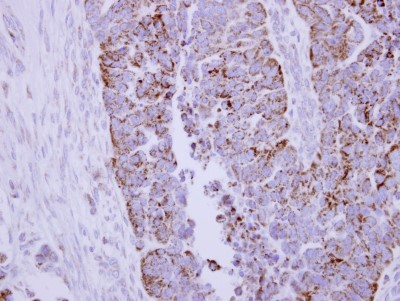

Supportive validation

- Submitted by

- Novus Biologicals (provider)

- Main image

- Experimental details

- Immunohistochemistry-Paraffin: Pyruvate Dehydrogenase E2 Antibody [NBP2-20026] - Immunohistochemical analysis of paraffin-embedded Ovarian carcinoma, using antibody at 1:250 dilution.